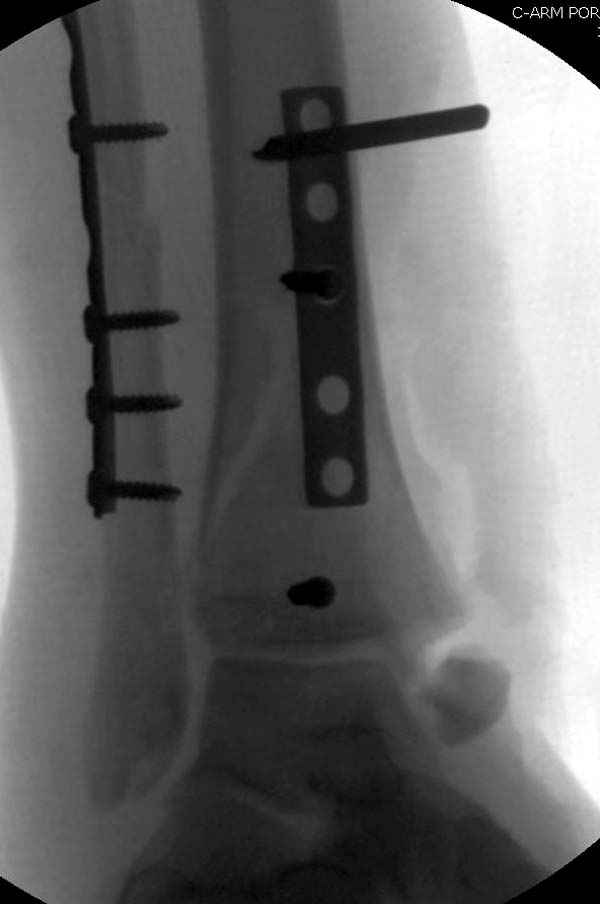

По снимкам довольно сохранный сустав, и такой сустав желательно попытаться восстановить всеми возможными мерами.

Артродез штифтом от Синтеза - немного агрессивно, а для улучшения качества жизни вместо артродеза голеностопа можно было бы предложить артродез подтаранного сустава. Тремя 6.5 мм каннюлированными шурупами через пятку.

Насчет пилона, прошло достаточное время для консолидации и прекрасная возможность для демонстрации, что такие случаи могут быть успешно вылечены остеотомией, несмотря на засторелость.

Из заднего доступа остеотомия тонким остеотомом и коррекции на ЭОПе.

Без применения сложной конструкции, а обычными параллельными шурупами. Шурупы в 3.5 мм и дополнительно фиксация крючковидной пластиной, сделанной из 3.5 mm semitubular пластиной, Butress или аntiglade фиксация.

Здесь алгоритм фиксации свежего перелома и преоперационный план для обсуждаемого случая.